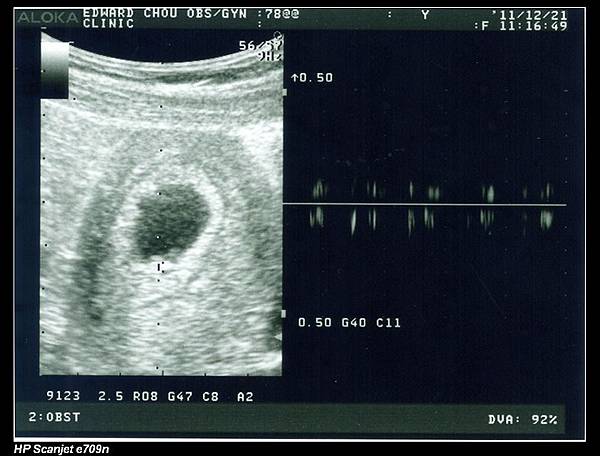

余小龍還很小,七週大,長度才0.74公分卻已有心跳,真是不可思議。

當周醫師將心跳聲放大讓我跟把拔聽時,我差點就要哭了,沒想到肚子裡真的有一個活跳跳的小生命耶!

下圖右方就是余小龍的心跳頻率。